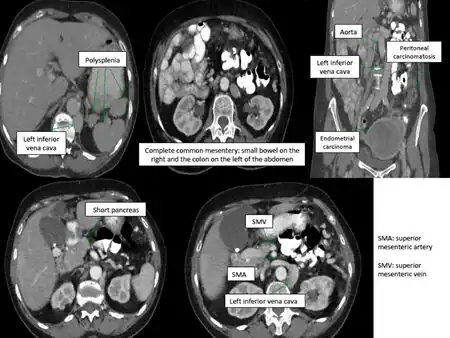

Situs ambiguus is a rare congenital defect in which the major visceral organs are distributed abnormally within the chest and abdomen. Clinically heterotaxy spectrum generally refers to any defect of Left-right asymmetry and arrangement of the visceral organs; however, classical heterotaxy requires multiple organs to be affected. This does not include the congenital defect situs inversus,[1] which results when arrangement of all the organs in the abdomen and chest are mirrored, so the positions are opposite the normal placement. Situs inversus is the mirror image of situs solitus, which is normal asymmetric distribution of the abdominothoracic visceral organs. Situs ambiguus can also be subdivided into left-isomerism and right isomerism based on the defects observed in the spleen, lungs and atria of the heart.

Abdominal organs, including the liver, stomach, intestinal tract, and spleen may be randomly arranged throughout the left-right axis of the body. Distribution of these organs largely dictates treatment, clinical outcomes, and further evaluation.

Random positioning of the stomach is often one of the first signals of situs ambiguus upon examination. Malrotation of the entire intestinal tract, or improper folding and bulging of the stomach and intestines, results in bowel obstruction. This impairment leads to vomiting, abdominal distension, mucus and blood in the stool. Patients may also experience abdominal pain. Intestinal malrotation is more commonly identified in patients with right atrial isomerism than in those with left atrial isomerism.

Isomeric patients often experience disruptions to splenic development during embryogenesis, resulting in an overall lack a spleen (asplenia) or development of many spleens (polysplenia). Asplenia is most often observed in patients with right atrial isomerism. Polysplenia results in 90% of patients with left atrial isomerism. Although they have many spleens, each is usually ineffective resulting in functional asplenia. Rarely, left atrial isomeric patients have a single, normal, functional spleen. Patients lacking a functional spleen are in danger of sepsis and must be monitored.[2]

- Deranged abdominal organ asymmetry:

- The stomach and spleen are prone to isolated reversal

- The stomach, liver, and a single adrenal gland are occasionally found in the midline.

- More rarely, the head of the pancreas fails to form

- Vascular abnormalities:

- Interrupted inferior vena cava,

- Bilateral superior or inferior venae cavae

- Intrahepatic interruption of the inferior vena cava with connection to the azygos or hemiazygos veins